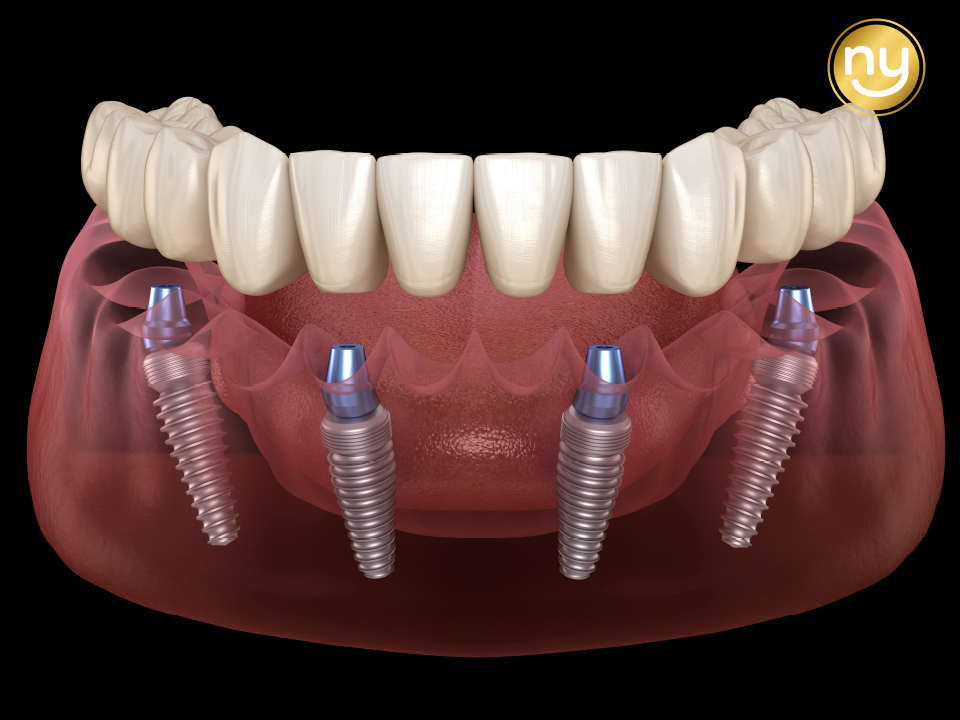

상악 구치부의 경우 오른쪽 3개, 왼쪽 2개를 식립하여

어금니의 역할을 수행할 수 있도록 제작해드렸는데요.

상악의 경우 잇몸뼈가 많이 소실되어 있는 상태라

길이가 짧은 임플란트를 사용하여 식립하였고

별도의 뼈이식 없이 임플란트 식립을 진행하였습니다.

하악에는 전치부 2개, 구치부 각 오른쪽 4개,

왼쪽 3개의 임플란트 식립으로 총 12개 치아의 기능을 회복하였습니다.

위아래 모두 12개씩 총 24개의 치아 기능을 회복하였습니다.